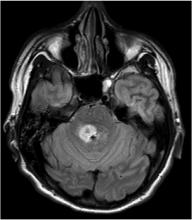

Leksell Radiosurgery Award winner Deborah C. Marshall presented her research, “Survival Patterns of Patients with Cerebral Metastases after Multiple Rounds of Stereotactic Radiosurgery” (SRS), at the 2015 American Association of Neurological Surgeons Annual Scientific Meeting.